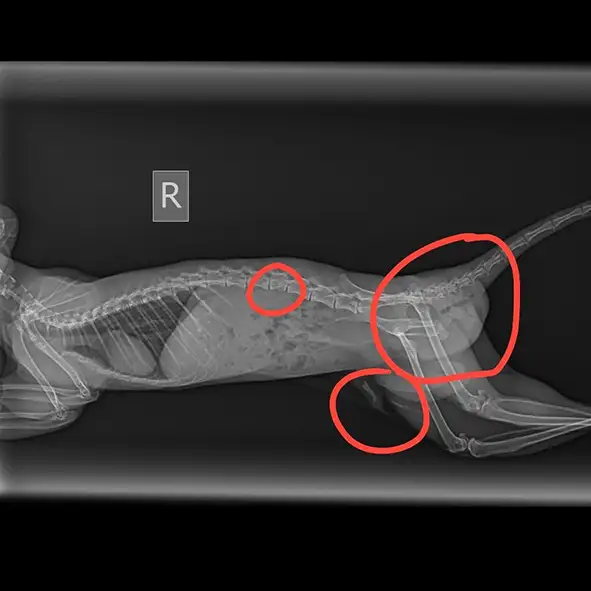

Найдена в лесу с повреждением задних лап. Лечение под контролем нашего веткорпуса

Найдена в парке с травмой задних лап. Консультация нашего врача. Нашедшие будут лечит

Получила травмы при падении. Парез задних конечностей. Спасти не удалось

Упала с дерева. Диагностировали перелом позвоночника. Лечили 3 недели. Не спасли

Поступил в ПБС с повреждениями задних конечностей. Терапия не помогла

Парез задних конечностей. Прошла лечение в клинике. Сейчас на реабилитации. Невыпуск.

Отказ задних лап. Компрессионный перелом позвоночника. В Первом беличьем стационаре

Сильное повреждение крестцового отдела. Пытались спасти. Не выжил

Перелом позвоночника. Находится на лечении в клинике. Прогнозы осторожные

Белка из Химок

Травма позвоночника и ЧМТ. Повезли в клинику. Спасти не удалось